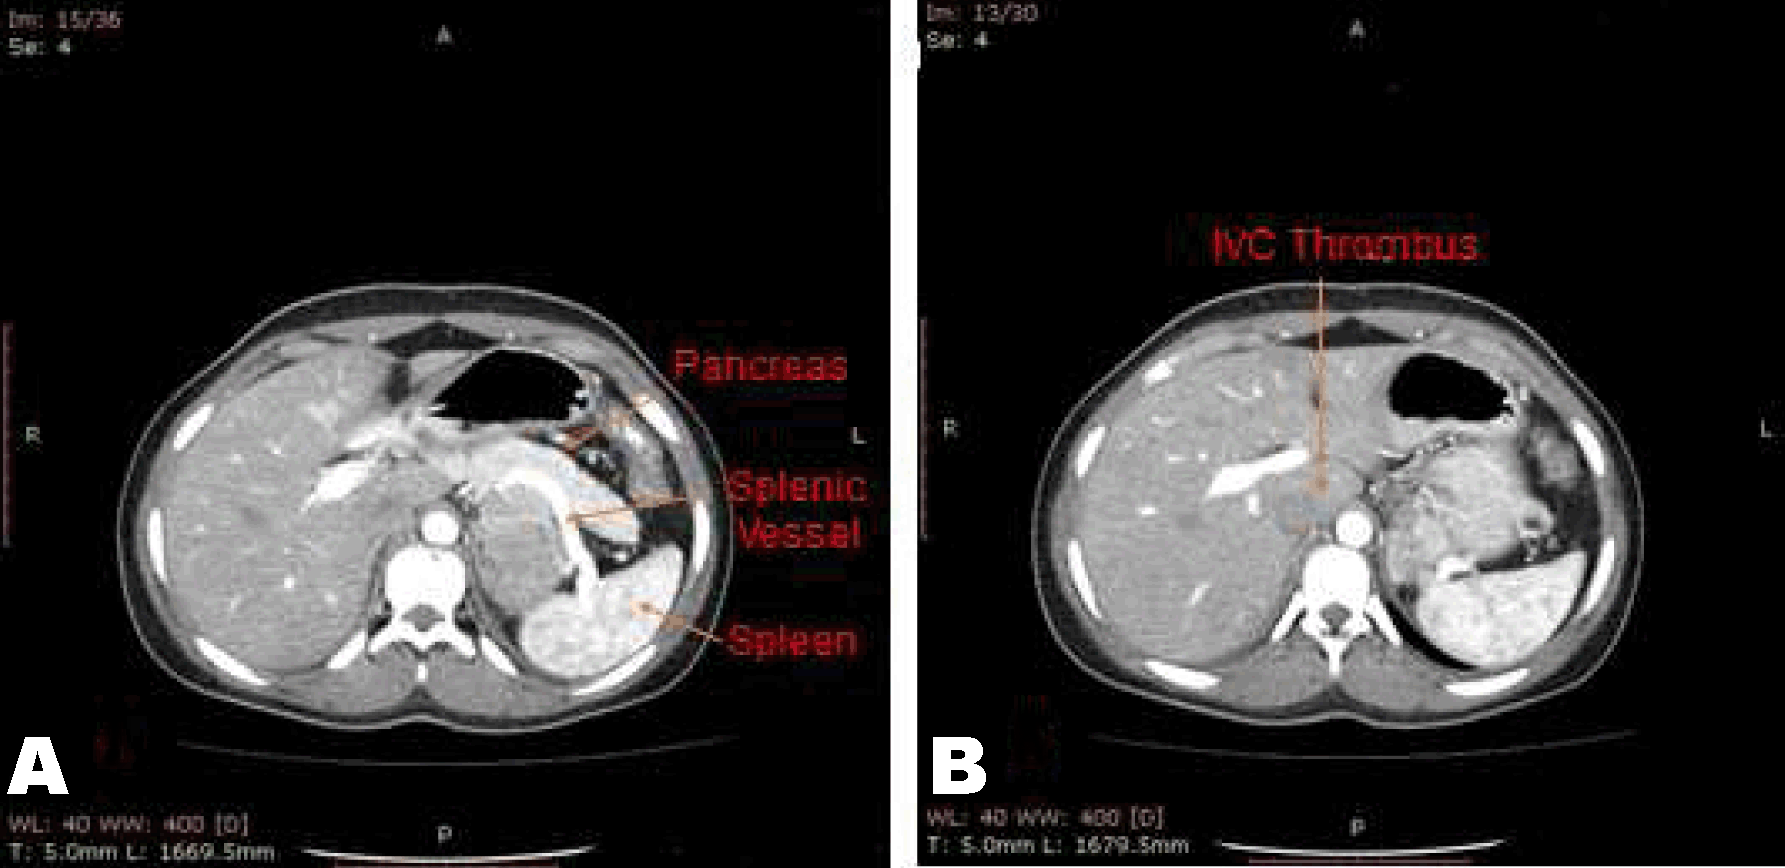

From www.cureus.com

Cureus Functional Adrenocortical Carcinoma A Rare Case With Thrombus How Rare Is Adrenal Cortical Carcinoma Acc starts in the outer layer of the. Adrenocortical carcinoma (acc) is a rare, aggressive malignancy with an annual incidence of ~1 case per million population. Acc usually occurs in the fifth or sixth. Adrenal cortical cancer (acc) is very rare. Adrenal tumors are found in about 1 in every 10 people who have an imaging test (like a ct. How Rare Is Adrenal Cortical Carcinoma.